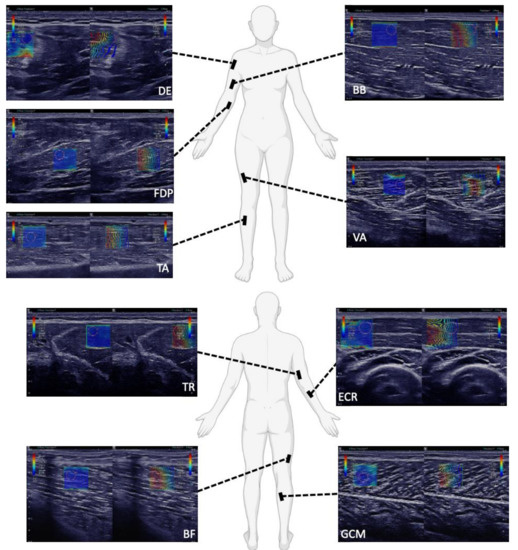

2.2. SWE Measurements and Subject Positioning

| DE | Supine, elbow resting on a pillow, arm bent at the elbow 90° | |||||||

| BB | Supine, elbow resting on a pillow, arm bent at the elbow 90° | Supine, elbow resting on a pillow, arm bent at the elbow 90° | Sitting, forearm resting, supinated underarm | Arm bent at the elbow 90° | Prone, 90° bent between legs and thighs | |||

| ECR | Supine, elbow resting on a pillow, arm bent at the elbow 90° | |||||||

| FDP | Supine, arm stretched out | |||||||

| TR | Left lateral recumbent | Arm at full extension | ||||||

| VA | Supine, legs almost completely stretched out with a small pillow under the knees | Supine, knees fully extended and feet slightly everted | Prone, lower extremity fully supported | Knee fully extended | Sitting upright, hip bent at 90° | |||

| BF | Sitting, feet flat on the floor | Prone, bent knees (90°), legs rested against a wall | ||||||

| TA | Sitting, lower leg free hanging | Supine, leg extended and heel on the examination table | Knee fully extended, ankle in neutral position | |||||

| GCM or GCL | Sitting, lower leg free hanging | Prone, feet relaxed, hanging from bed | Prone, lower extremity fully supported | Prone, hip and knee at ~ 0°, ankle at 20° plantar flexion | Supine, knee flexed and hip in external rotation | Knee bent at 90°, ankle in neutral position | Prone, 90° bent between legs and thighs | |